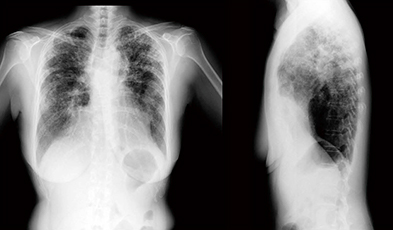

胸部単純X線写真では,上肺野優位の網状影,浸潤影が認められる。単純CT画像(図4)では,上肺野に強い網状影とコンソリデーションが認められた。胸部X線動態画像(図5)では全体的に動きが悪く,横隔膜の動きも不自然で,側面像では肺の下葉が呼吸を支えているという印象である。変位のベクトル表示画像(図6)でも肺野全体の動きが悪い印象であった。

図4 症例2:胸部単純CT画像

図5 症例2:胸部X線動態画像

図6 症例2:変位のベクトル表示画像